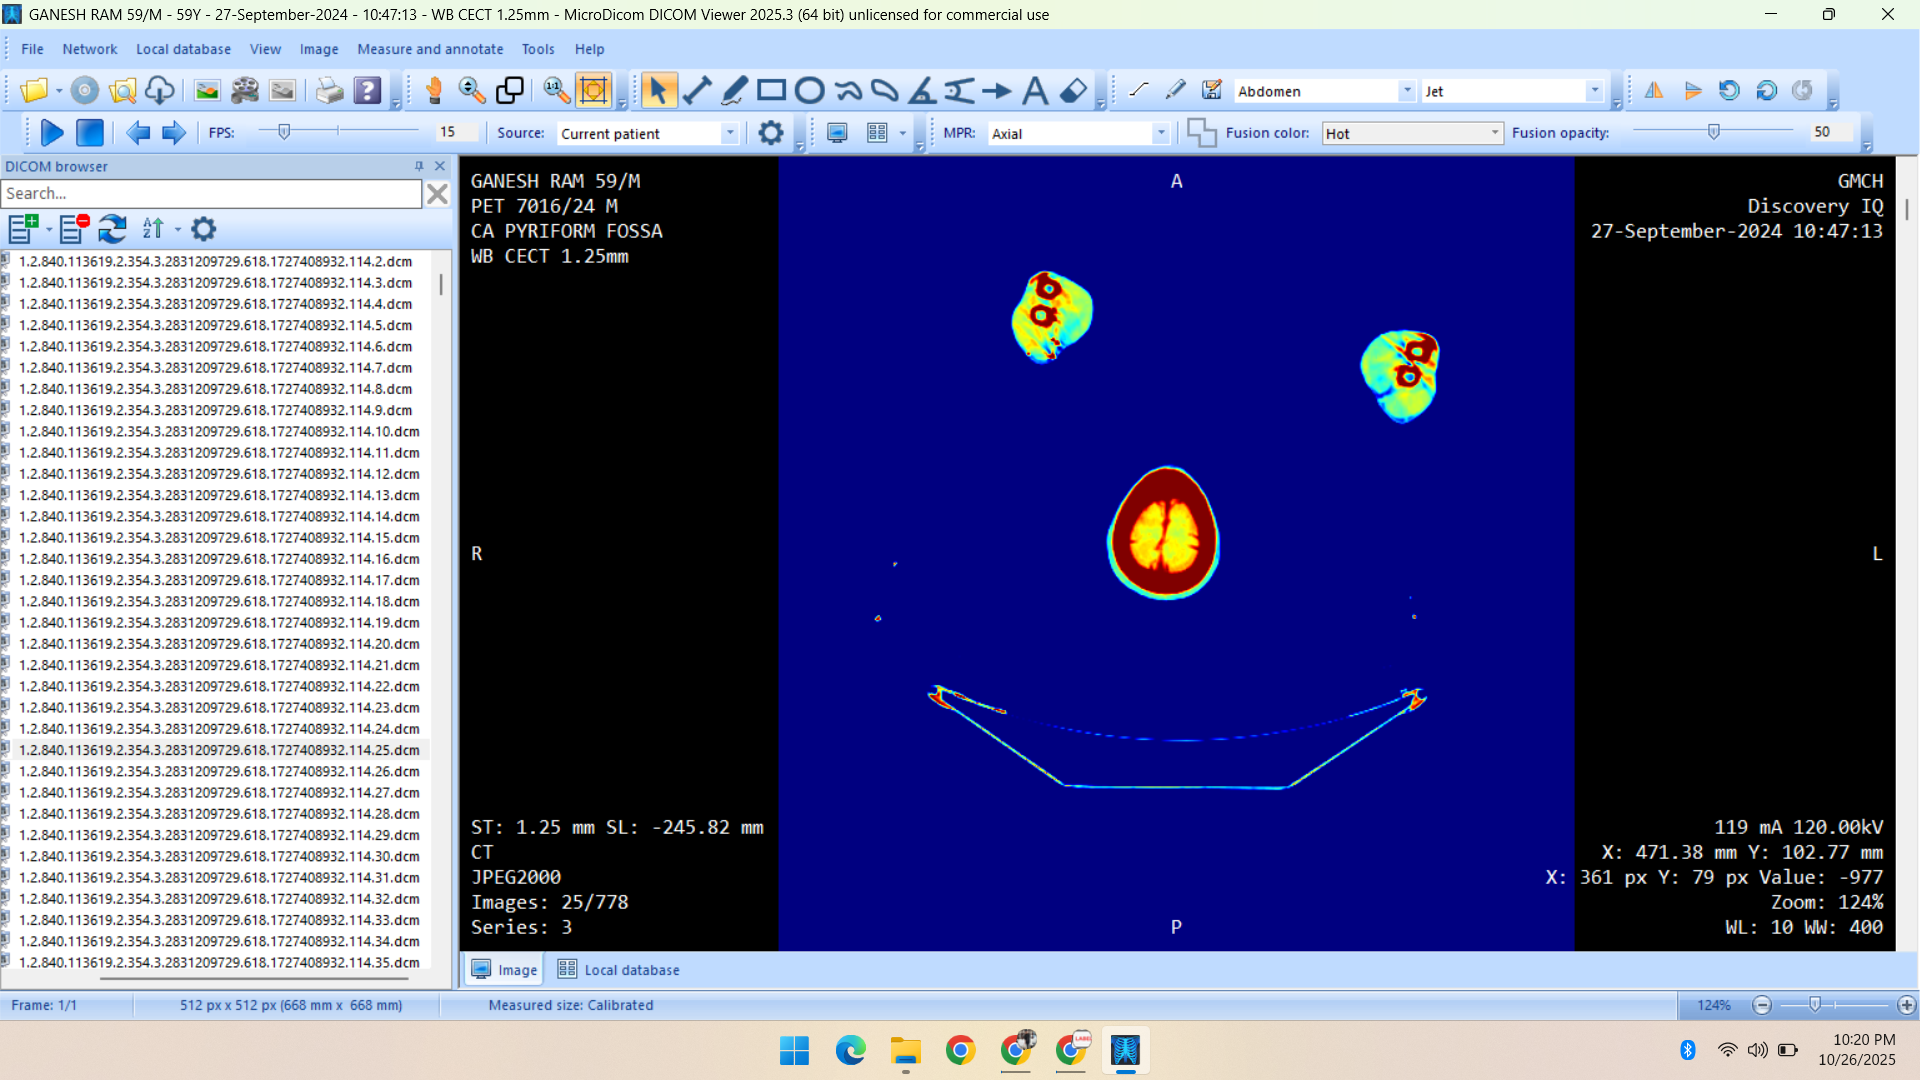

- Radiology Data – CT Scans, X-Rays, MRI, Echocardiography, Ultrasound.

Healthcare & Medical Data Supply

We specialize in healthcare datasets including radiology (CT, X-ray, MRI, Ultrasound, Echocardiography), pathology microscopy, and histopathology images — all ethically sourced and research-ready.

Portfolio

Showcasing Innovative AI Solutions and Data Services: Delivering Quality Data for Smarter, Future-Ready Applications

- CT Scan

- PET Scan